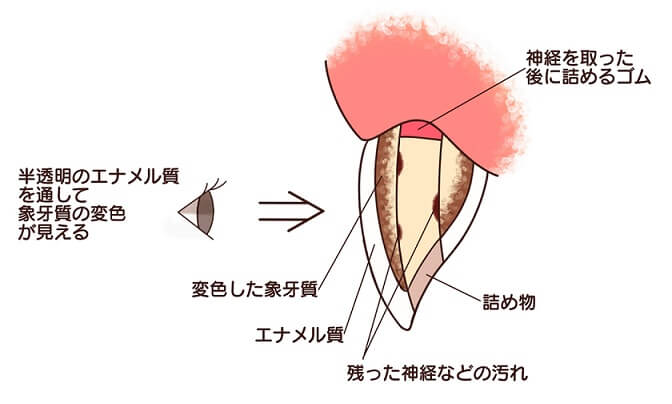

虫歯や事故など何らかの理由で神経を抜いた歯は、時間がたつと明度が下がり茶色~黒色に変色してきます。

原因は神経があることで健康だった歯が、神経がなくなることで血液の供給が止まり、象牙質のたんぱく質が変色したり、細菌に感染するなどの理由でくすんできます。

ちょうど枯れ木が茶色く変色してくるのと同じです。また歯の神経は歯の先端付近まで細い神経が通っており、神経を取る際に神経組織の取り残しや、出血した血が残っていると変色の原因になります。特に血液成分は鉄分が多く含まれていますので、血液が残っていると黒く変色してきます。

神経を取ってしまって変色した歯は、通常のホワイトニングでは白くなりにくく、また色戻りもしやすくなっています。変色の原因が神経組織の取り残しや血液成分による場合、その原因を取り除かない限り白くなりません。